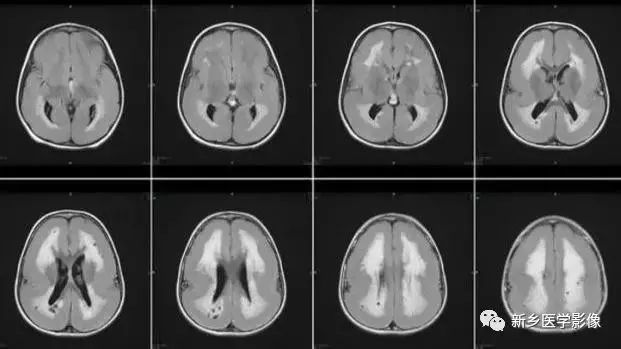

❻ 脑室周围白质软化症

主要与缺血缺氧及感染有关。

常见于早产儿。原因与胚胎期脑部损害发生的时间有关:胚胎早中期脑损害主要引发发育畸形,晚期主要引起脑血管改变。

由于侧脑室周围有软化萎缩,故扩大的侧脑室外缘常不规则、不光整,这种不规则、不光整是本病引起脑室扩大的特。另外,本病均表现有脑白质量减少及脑白质内斑片状软化病灶,脑白质减少严重时表现为部分区域白质消失,脑皮层与脑室侧缘接近甚至相连。CT表现为斑片状低密度灶。MR T1WI上呈低信号,T2WI呈高信号。